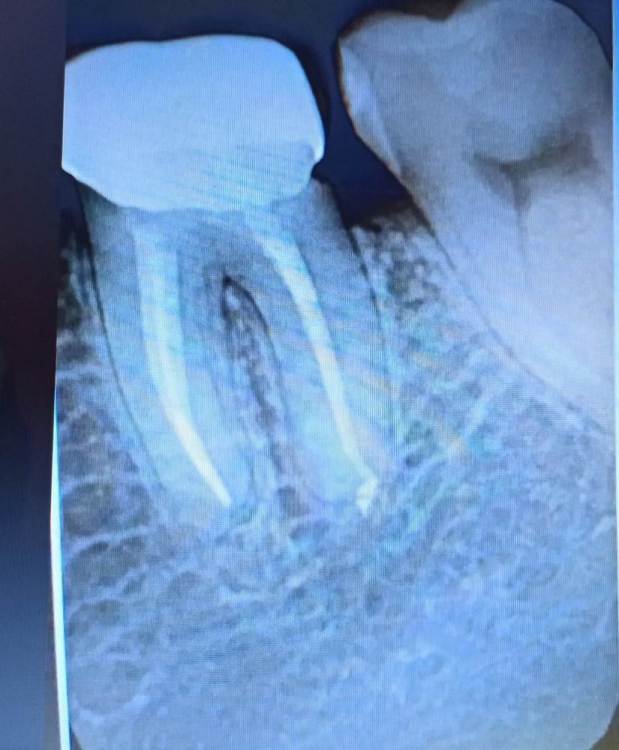

Привет, под коронкой справа откололся маленький кусочек зуба, теперь такой промежуток треугольничком(фото).

насколько важно или просто чистить теперь лучше и не париться, или пойти залечивать? Пломбой такое не закрывают,а то может там и трещинка по линии прилегания и микробы попадут?